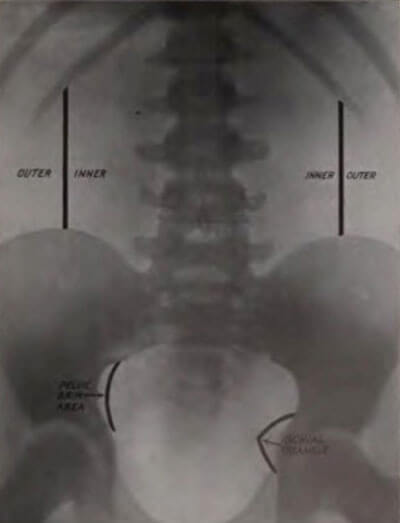

Figure 1: Fenwick’s suggestion of useful landmarks on a KUB x-ray.

Edwin Hurry Fenwick (1856-1944) published The Value of Radiography in 1908. Fenwick was a remarkable surgeon who expanded his research to encompass radiological and pathological findings in order to further his clinical understanding (Figure 1). His classic work is the result of 12 years of urological research into x-rays and compiles 80 radiographs each with a corresponding case report. It is an unequivocal endorsement for the adoption of clinical imaging in urological practice: “let us employ it routinely when it is possible, and control its findings by operative work.”